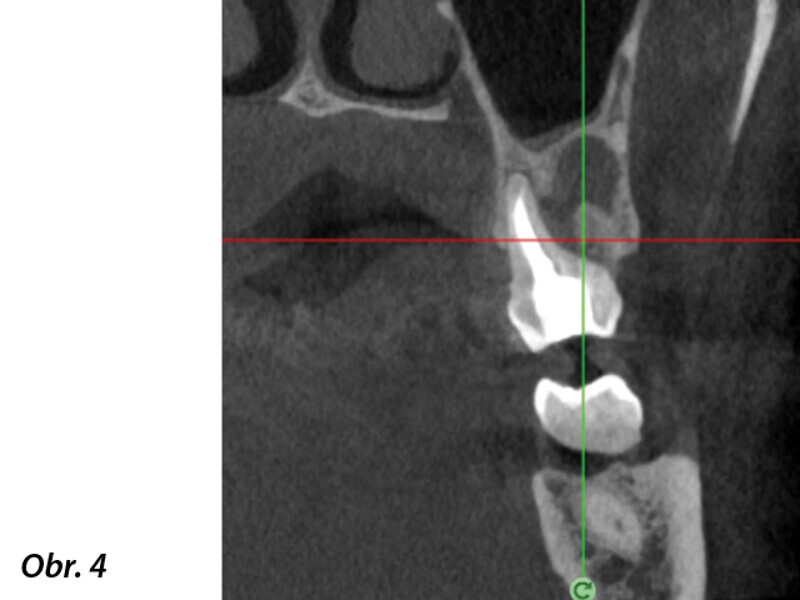

3D technologie v diagnostice a léčbě endodontických onemocnění